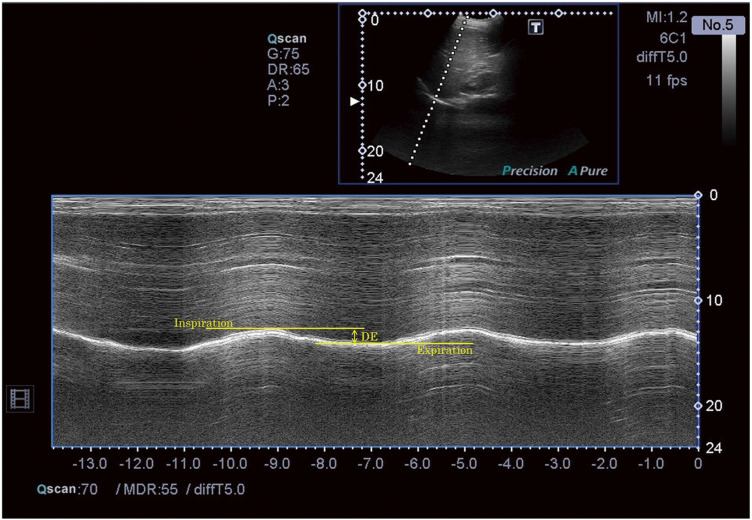

Objective: The movement of the diaphragm plays an important role in respiration. In this study, we proposed and validated a new method for estimating the volume of a single ventilation (representing the tidal volume [VT]) from the vertical distance of diaphragmatic movement and thoracic circumference.

Method: Diaphragm excursion (DE) was measured in healthy adult subjects via ultrasound, and the thoracic cavity volume change was estimated based on DE and thoracic circumference. Moreover, we measured the VT obtained by an expiratory gas analyzer and examined the relationships between DE and thoracic volume change (TVC) and between DE and VT.